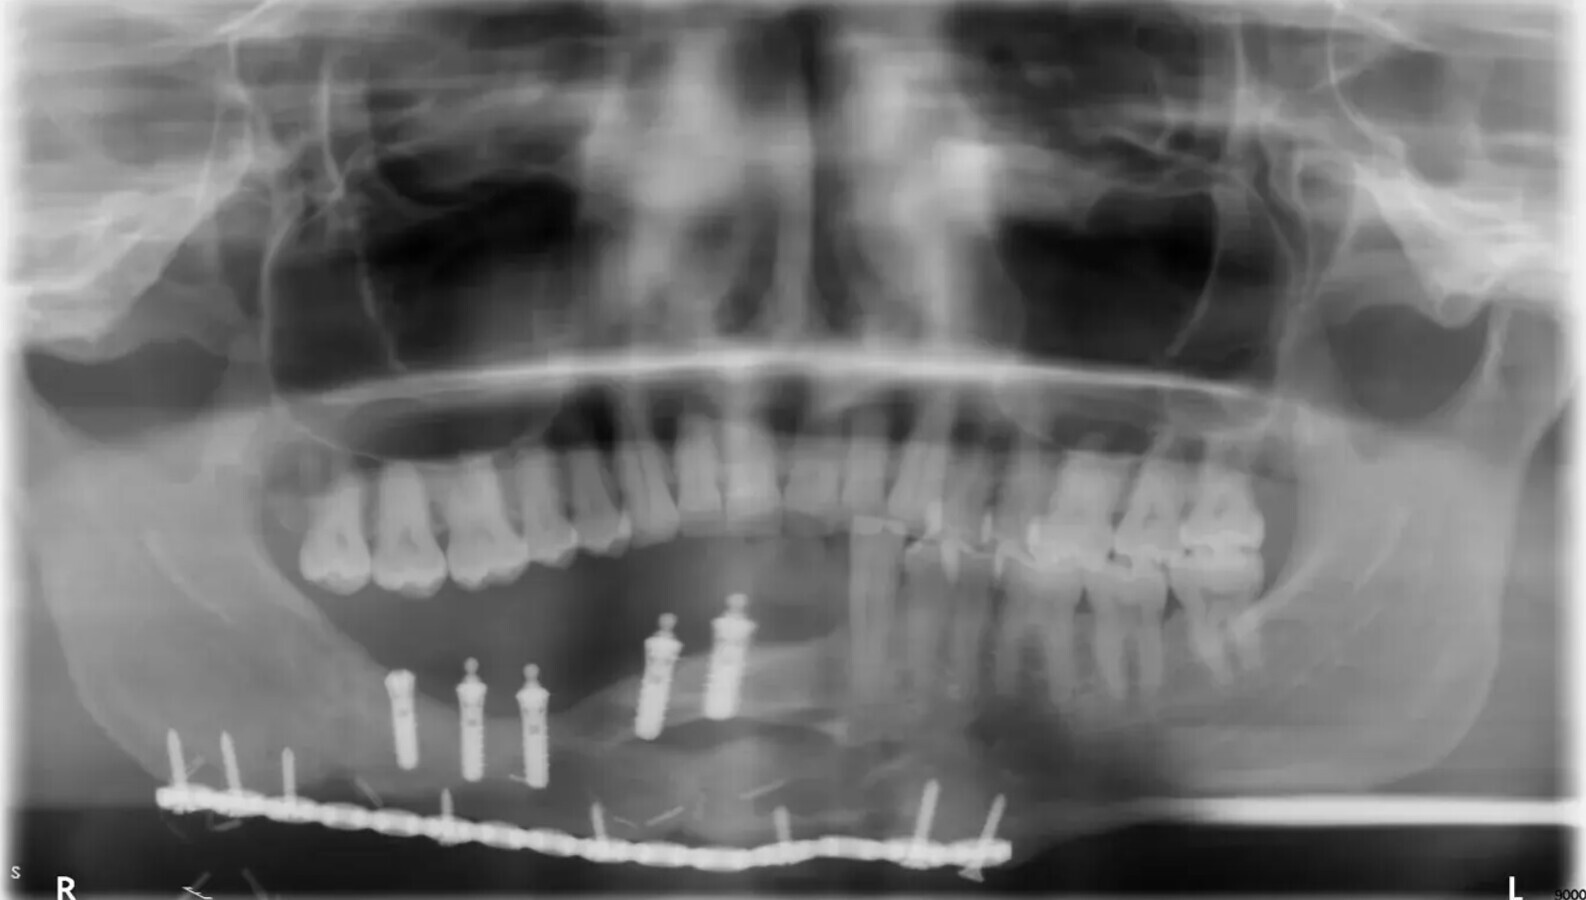

Fig. 2: OPG di un paziente di 9 anni dopo la riabilitazione dentale supportata da impianto. Si osservano i livelli ossei marginali stabili.

Fig. 3: quadro clinico intraorale dello stesso paziente. Notare la presenza di mucosa cheratinizzata sana attorno agli impianti nella mandibola ricostruita dal lembo libero dal perone.